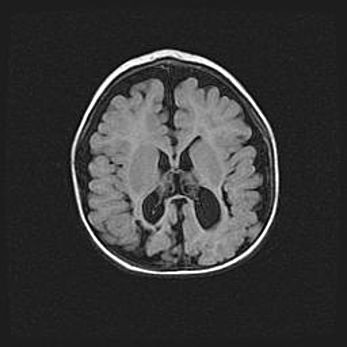

Лейкомаляция с кистозно-глиозной дегенерацией головного мозга.

Возраст: 2 месяца 25 дней

Вес: 6400 г

Окружность головы: 40 см

Срок гестации: 41 неделя

Лейкомаляцию относят к ишемически-гипоксическим повреждениям головного мозга, диагностируемым у новорожденных. При лейкомаляции в головном мозге обнаруживают очаги некроза, возникшие после тяжелой гипоксии и нарушения кровотока. В процессе морфогенеза очаги проходят три стадии: 1) развития некроза, 2) резорбции и 3) формирования глиозного рубца или кисты. Перивентрикулярная лейкомаляция (ПЛ) встречается примерно в 12% случаев среди новорожденных, обычно – у недоношенных детей, причем, частота ее зависит от массы, с которой младенец появился на свет. Наибольшее число малышей страдает лейкомаляцией, если масса при рождении 1500-2500 г.